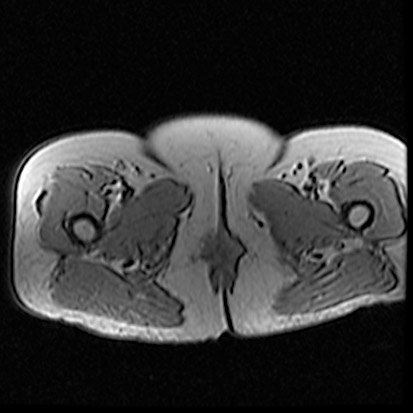

Хорошая дифференциация мягких тканей, особенно с использованием контраста. Более высокое разрешение картинки, благодаря скорости отображения.

Исследования мягких тканей, повреждения сухожилий и связок, травмы позвоночника, опухоли головного мозга и т.д…

Более высокая детализация мягких тканей по сравнению с КТ. Просматривается малозаметная разница между разными по составу тканями.

• МРТ дает более детальное изображение мягких тканей.